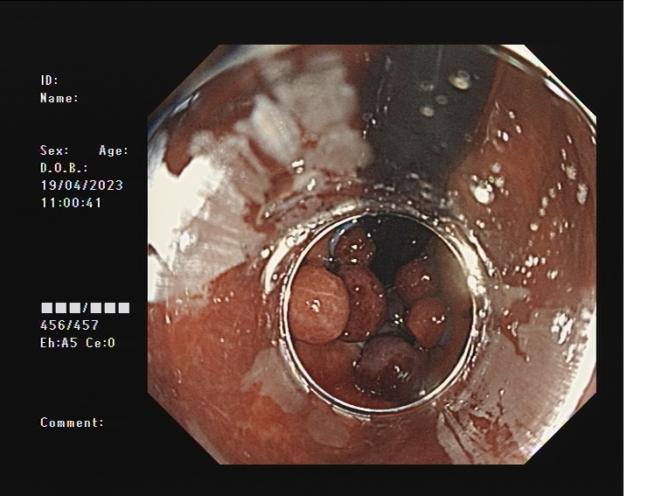

胃底靜脈曲張 內鏡下組織膠粘合術

胃底靜脈曲張組織膠粘合術(HI):治療胃底食管靜脈曲張,防止靜脈曲張破裂出血,降低因肝硬化導致胃底靜脈曲張破裂引起的致命風險。